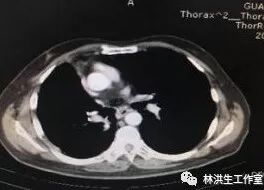

【诊断】右肺腺癌术后,左肺门及纵膈淋巴结转移,多程化疗后 Ⅲ期

【现病史】患者2011年8月诊断右肺上叶中低分化腺癌Ⅲ期,行右肺上叶切除术后行5周期GP方案辅助化疗,后定期复查胸部CT,病情稳定。2015年1月22日胸部CT提示:右肺下叶近肺门可见形态不规则肿物影,大小约3*3.5cm,纵膈及左肺门可见多发淋巴结影,考虑进展,予中西医结合治疗至今,病灶控制稳定,体力状况PS 100分。